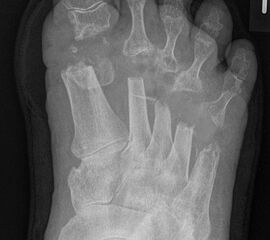

Es handelt sich bei dem „rheumatischen Vorfuß“ nicht um eine „normale“, meist rein mechanische Metatarsalgie, sondern um eine durch Synovialitiden sich häufig schnell entwickelnde und sehr ausgeprägte komplexe Fehlstellung. Die persistierend chronische Entzündung mit hoher Aktivität führt zu einer Veränderung oder Verlust der Sehnenfunktion mit Ruptur der plantaren Platte und Ligamente, subchondralen Usuren, Knorpel- und Knochendeformationen. (siehe auch Kapitel "Die Stainsby OP" von Briggs P, Stainsby D - Abschnitt "Pathomechanik des deformierten Rheumafußes").

Die Resektion der Metatarsaleköpfe ist dann indiziert, wenn bei Destruktion der Metatarsophalangealgelenke (LDE IV und V - siehe Tabelle 1) keine gelenkerhaltenden Alternativen zur Verfügung stehen.